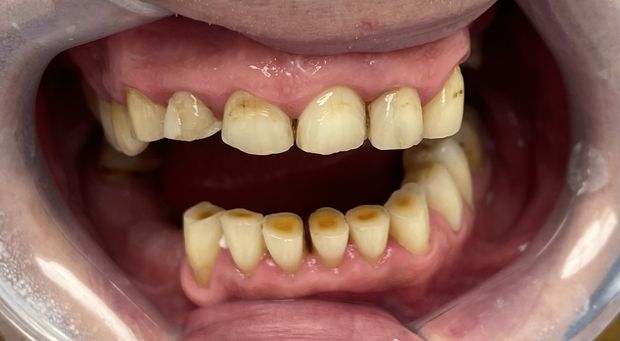

Pełna rekonstrukcja łuków zębowych, podwyższenie zgryzu, odbudowa utraconych tkanek zębów z wykonaniem koron cyrkonowych licowanych ceramiką oraz ruchomych uzupełnień protetycznych.